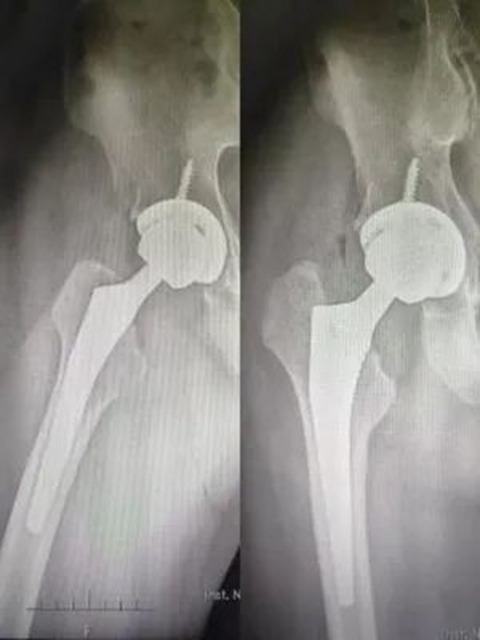

蒋先生术后1天开始下地行走功能锻炼

蒋先生术后X片